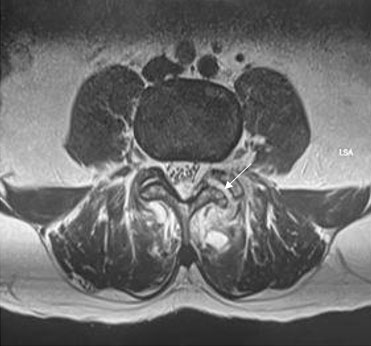

Case Report: A 48-year-old male was diagnosed with an advanced mixed germ cell tumor of the right testis with markedly elevated human chorionic gonadotropin levels. Induction and second-line chemotherapy with platinum-based regimens did not achieve normalization of the tumor marker. As salvage chemotherapy, a regimen of 5-fluorouracil and actinomycin D was applied, which led to remission of the tumor marker. However, additional consolidation courses were discontinued due to cumulative adverse events and the patient’s wishes. Ultimately the patient died of tumor recurrence.